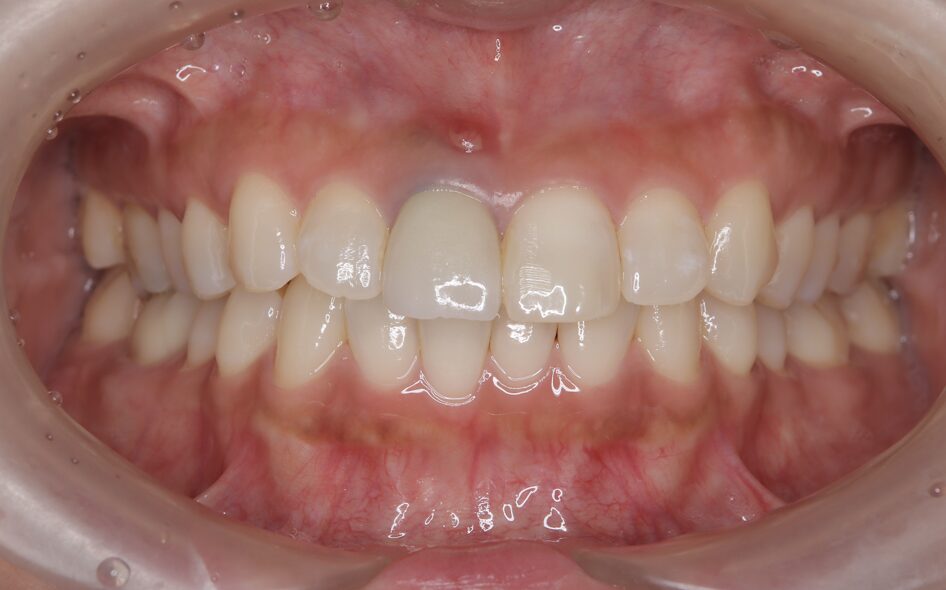

初診時の状態|前歯の歯ぐきに腫れとできものが見られました

初診時、右上の前歯周囲には炎症による腫れが見られました。

歯の根の中で破折が起こり、そこから細菌が侵入したことで、根の先に膿がたまっている状態でした。

初診時の口腔内写真①

最終補綴物の装着|自然な見た目と噛み心地を回復

治療期間中は仮歯を装着し、歯の形・色・歯ぐきとの調和・噛み合わせを確認しながら調整しました。

最終的に、インプラント上にセラミッククラウンを装着し、前歯としての見た目と機能の回復を図りました。

術前後の比較